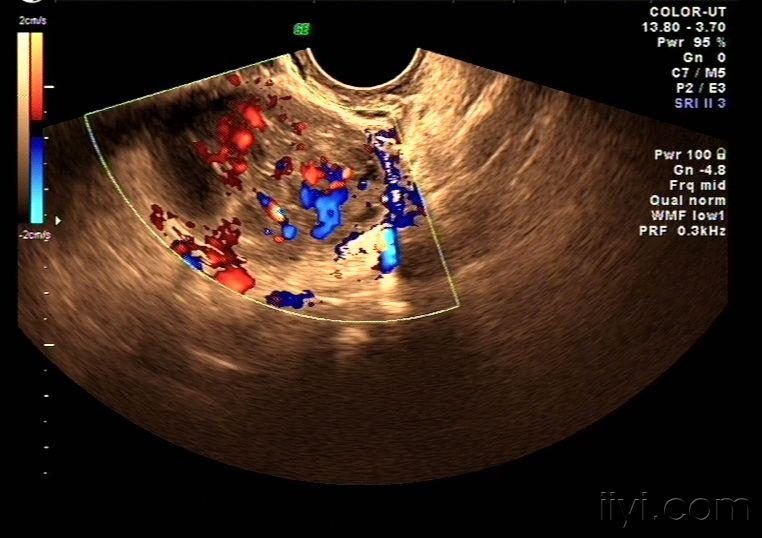

一例卵巢腺癌超声图像

图片尺寸683x504